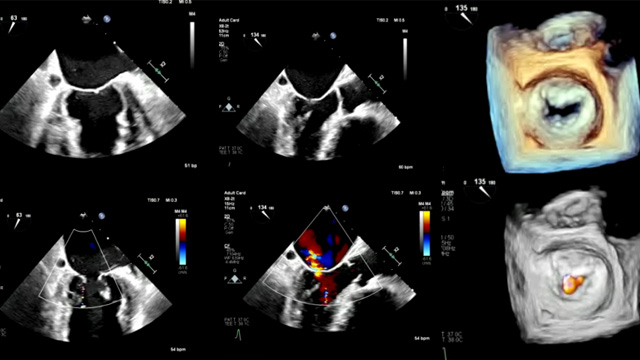

Challenging situations in M-TEER: Takotsubo syndrome

Dive into this session to explore challenging situations in Mitral Transcatheter Edge-to-Edge Repair (M-TEER). Discover case studies showcasing a range of complex scenarios, including Takotsubo syndrome following M-TEER, successful TEER with improved visualization using a bronchial blocker, managing cardiac arrest during MitraClip procedures, and more. Gain...

Tips and tricks for M-TEER

Discover valuable tips and tricks for Mitral Transcatheter Edge-to-Edge Repair (M-TEER) in this session. Learn about navigating difficult transseptal access through a left-atrial septal pouch, managing severe mitral regurgitation in an octogenarian with scoliosis and kyphosis, and innovative techniques like diamond-shape clasping using the PASCAL device....

Mitral challenging anatomy

Explore this session to discover various challenging mitral valve anatomies and interventions. From unavoidable iatrogenic mitral stenosis following transcatheter edge-to-edge repair to successful procedures with the PASCAL device for severe mitral regurgitation, this session provides valuable insights into complex mitral valve cases.